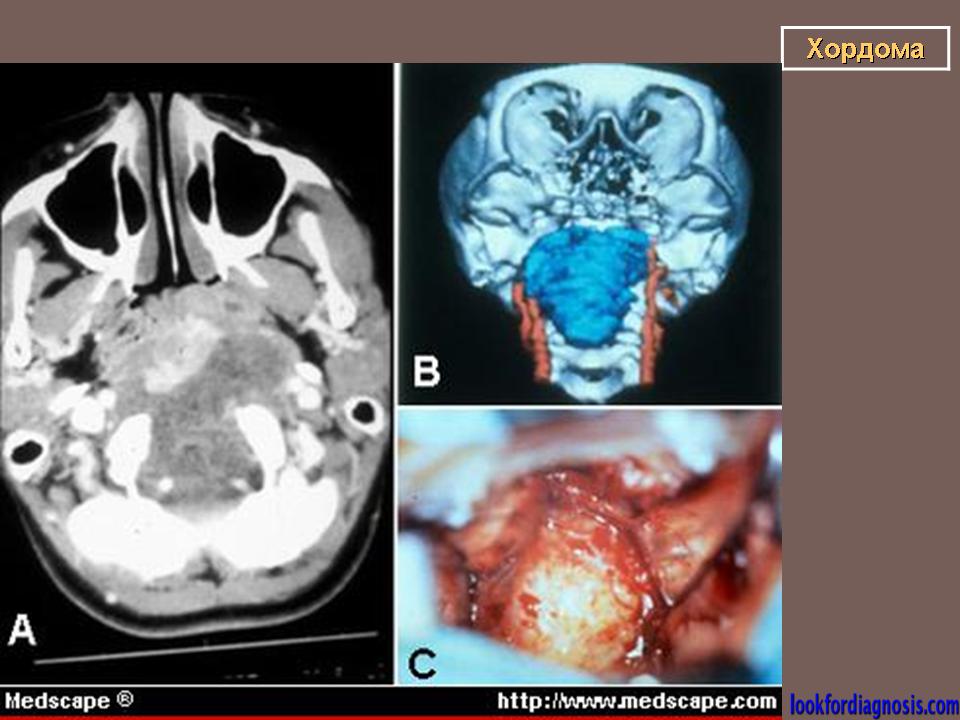

Хордома развивается из персистирующих остатков хорды. Преимущественная локализация хордомы - это область сфеноокципитального сочленения и крестцово-копчиковый отдел позвоночника. Сведения о частоте отдельных форм хордомы весьма разноречивы.

Рентгенологическая картина хордом характеризуется наличием очага деструкции, захватывающего ряд позвонков. Костный дефект представляется однородным, либо крупнокамерным за счет тонких костных полосок. Показаны боковые рентгенограммы крестца, на которых при хордоме определяется увеличение передне-заднего размера крестца за счет экспансивного роста опухоли. В отдельных случаях в опухоли прослеживаются небольшие костные включения, которые могут служить поводом для ошибочной диагностики тератом, особенно в детском возрасте. (В детском возрасте тератомы встречаются часто, их соотношение с хордомами, по данным М. В. Волкова, 60:2).

Лечение хордом - оперативное. В случаях нерадикального хирургического вмешательства могут возникать рецидивы опухоли.